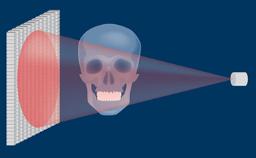

The use of dental implants has become a standard treatment in many clinical situations. However, in order to achieve optimal functional and esthetic results, the clinician has to assess the complexity and risks associated with an implant therapy before starting the treatment.

The SAC classification system differentiates between Straightforward, Advanced and Complex treatments. It was first proposed in a textbook on minor oral surgery for general dentists. In a Consensus Conference in 2007, the ITI reviewed and refined the SAC Classification for use in implant dentistry. The proceedings were published in a text book in 2009 and since then serve as an important tool in implant dentistry.